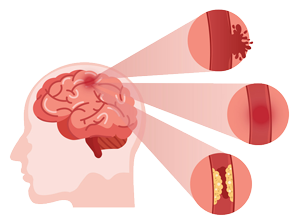

BE FAST

Balance

Loss of balance

Eyes

Blurred Vision

Face

One side of the face is drooping

Arms

Arm or leg weakness

Speech

Speech Difficulty

Time

Time to call for help

STROKE IS NO JOKE

If you notice any symptoms, immediately reach out and get the required treatment. Quickest treatment ensures that you can go back to life as usual.